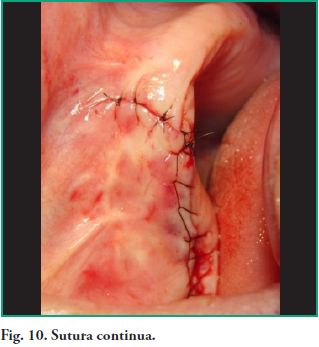

Se procede a hacer ostectomía con instrumental rotatorio y abundante irrigación con suero fisiológico, con la finalidad de agrandar la fenestración para facilitar la visibilidad. Con curetas de elevación sinusal se realiza la eliminación total de la lesión mediante la técnica de enucleación y curetaje, procediendo luego a hacer la exéresis del tabique óseo que divide dicha patología (Figs. 7, 8, 9). Por último se realizó un cierre mediante sutura continua con nylon 5 cero (Fig. 10).